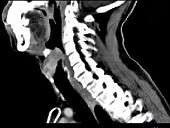

- 单项选择题男,53岁, 咽部不适半年余,近两个月感咽部疼痛, 声嘶,CT如图所示, 应诊断是 ( )

D、喉癌

E、梨状窝癌